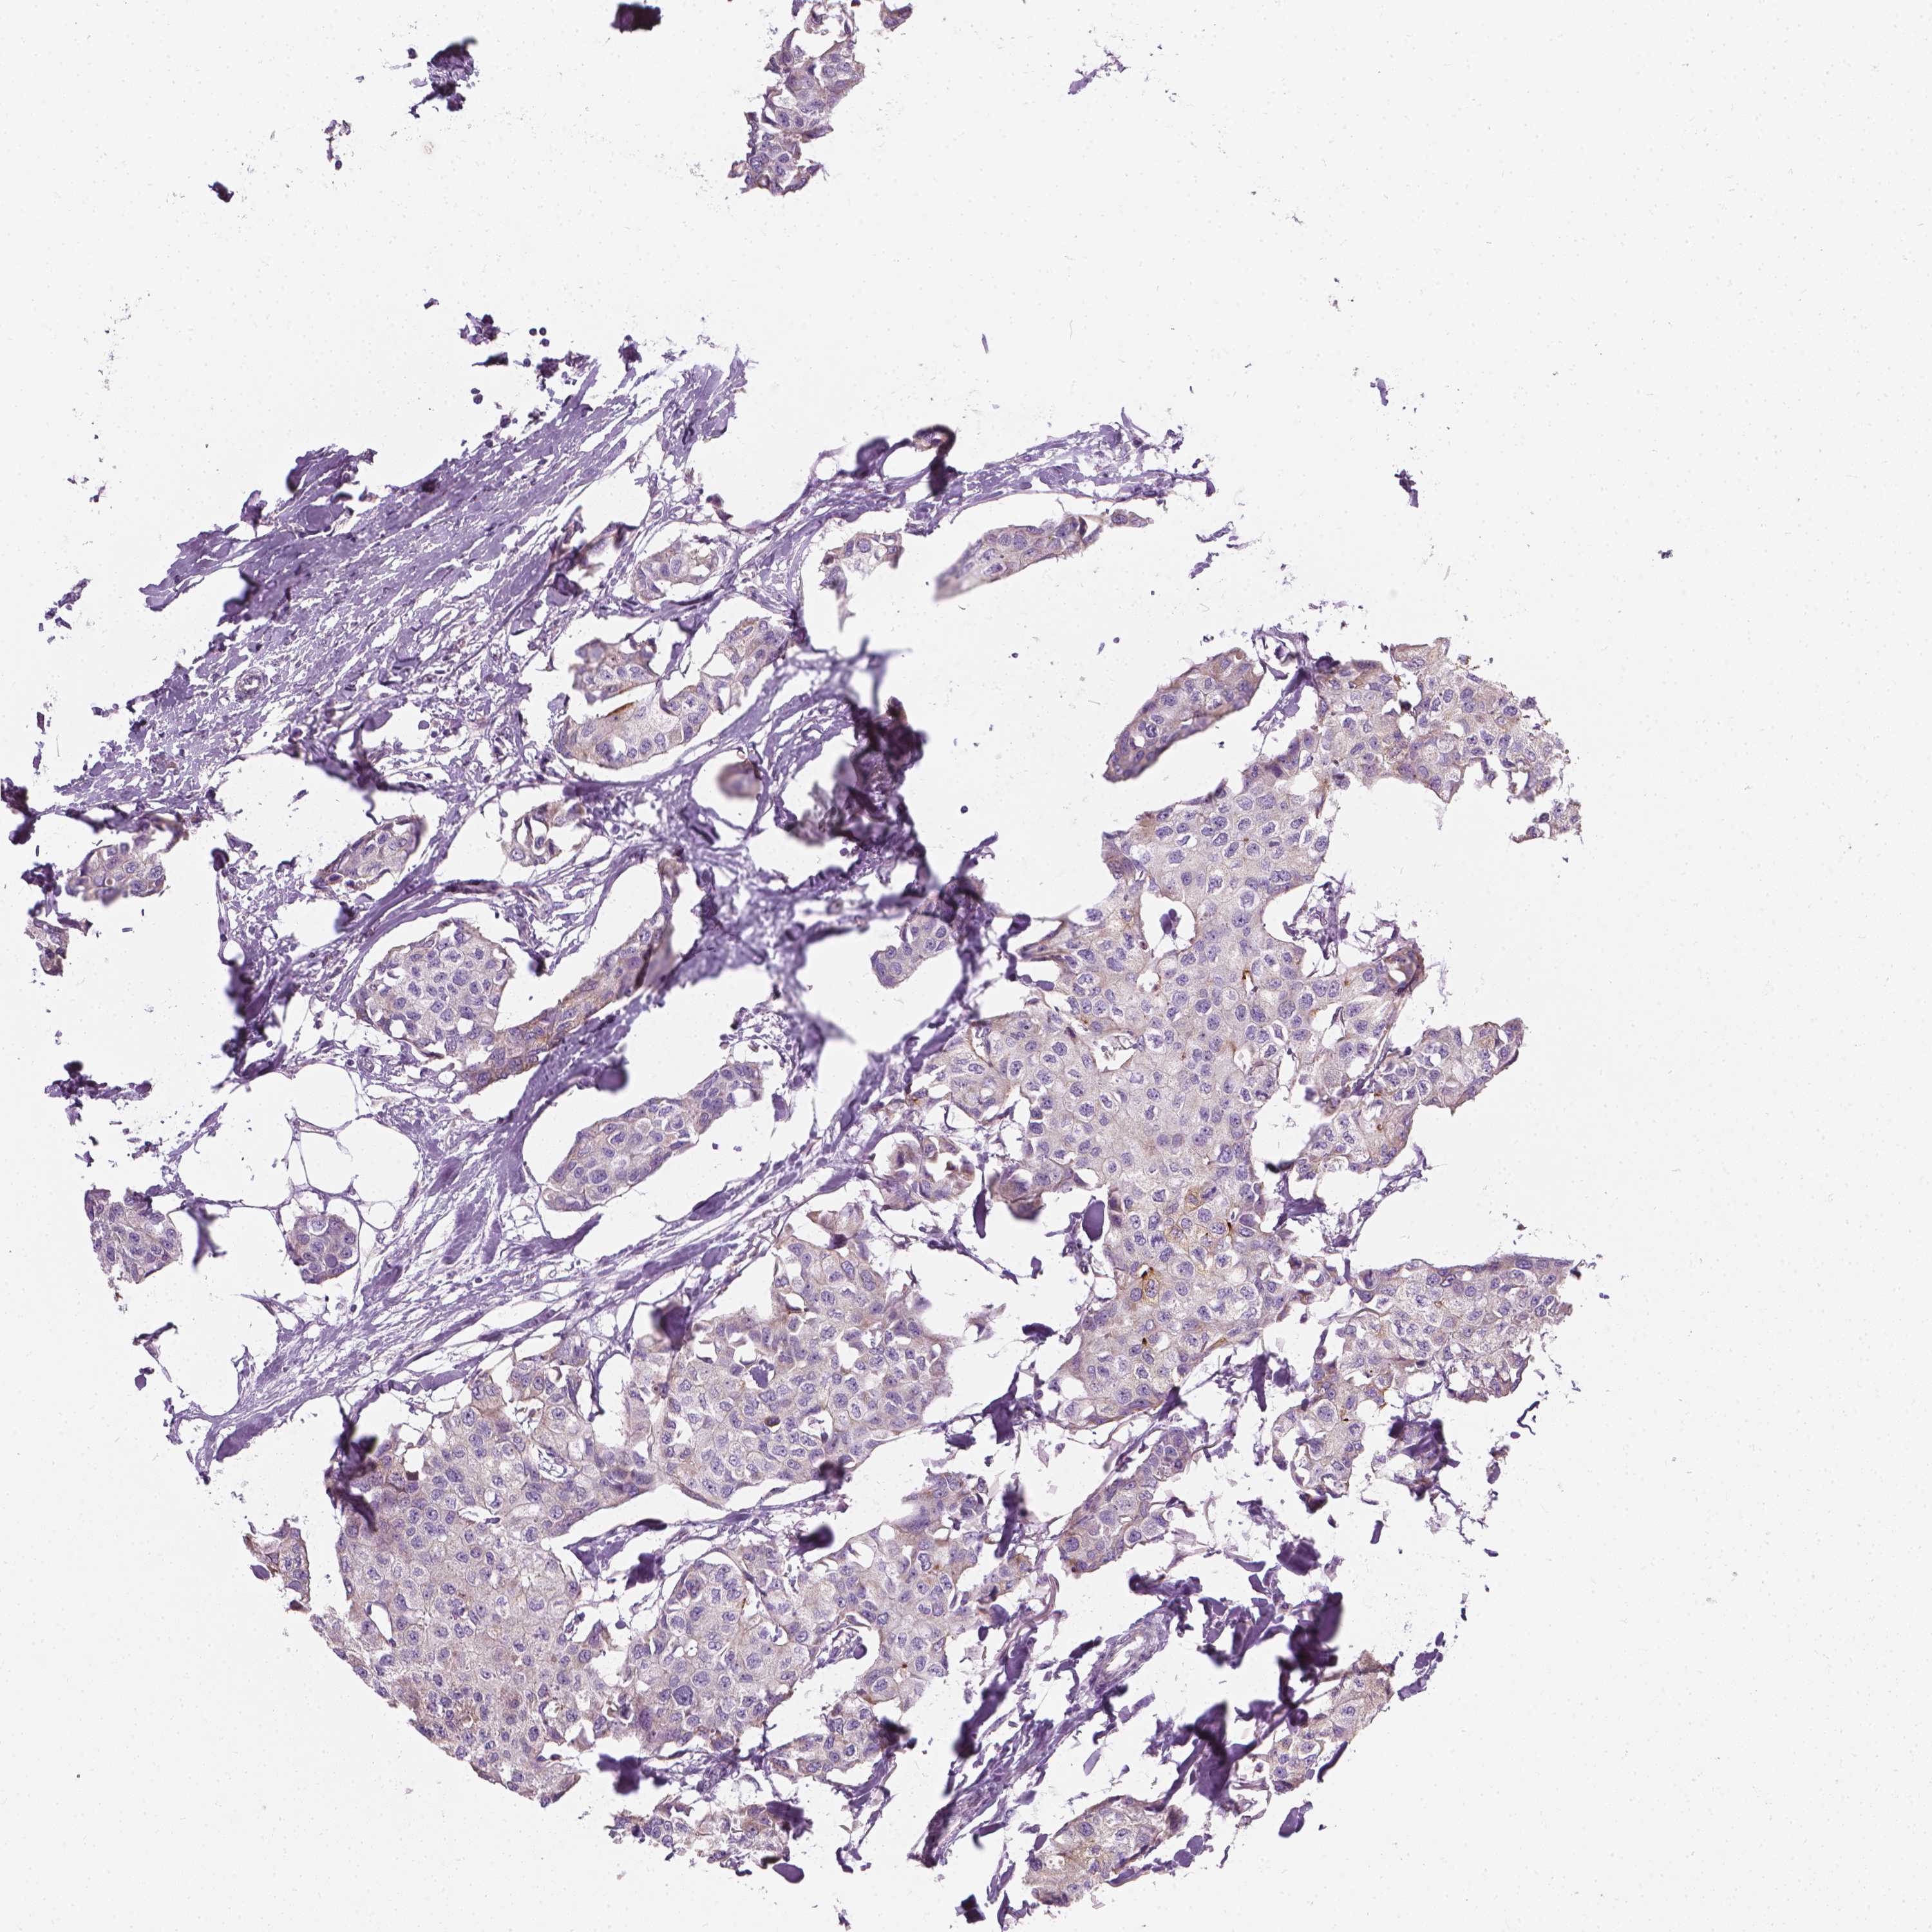

CANCER BREAST CANCER Show tissue menu

BRCA TCGA BRCA VALIDATION PROTEIN EXPRESSION